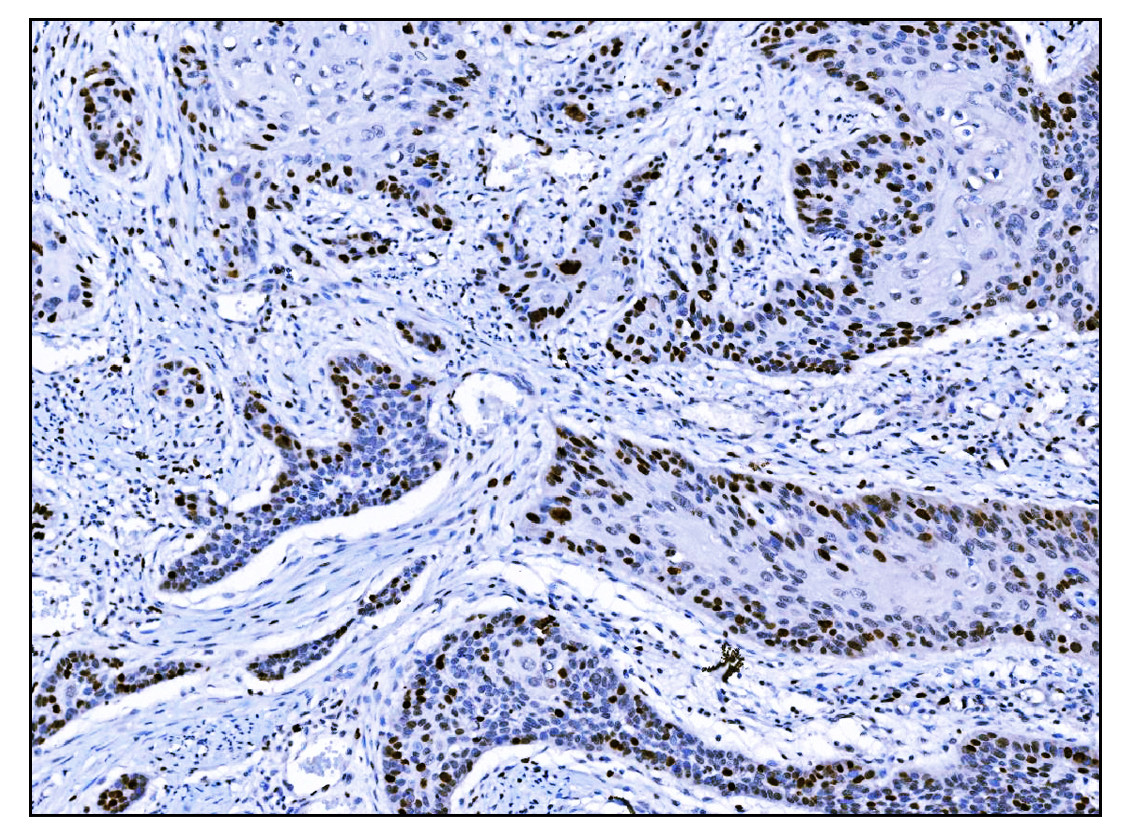

IHC analysis of Ki67/MKI67 using anti-Ki67/MKI67 antibody (M00254-8).

Ki67/MKI67 was detected in a paraffin-embedded section of human cervical cancer tissue. Biotinylated goat anti-mouse IgG was used as secondary antibody. The tissue section was incubated with mouse anti-Ki67/MKI67 Antibody (M00254-8) at a dilution of 1:200 and developed using Strepavidin-Biotin-Complex (SABC) (Catalog # SA1021) with DAB (Catalog # AR1027) as the chromogen.